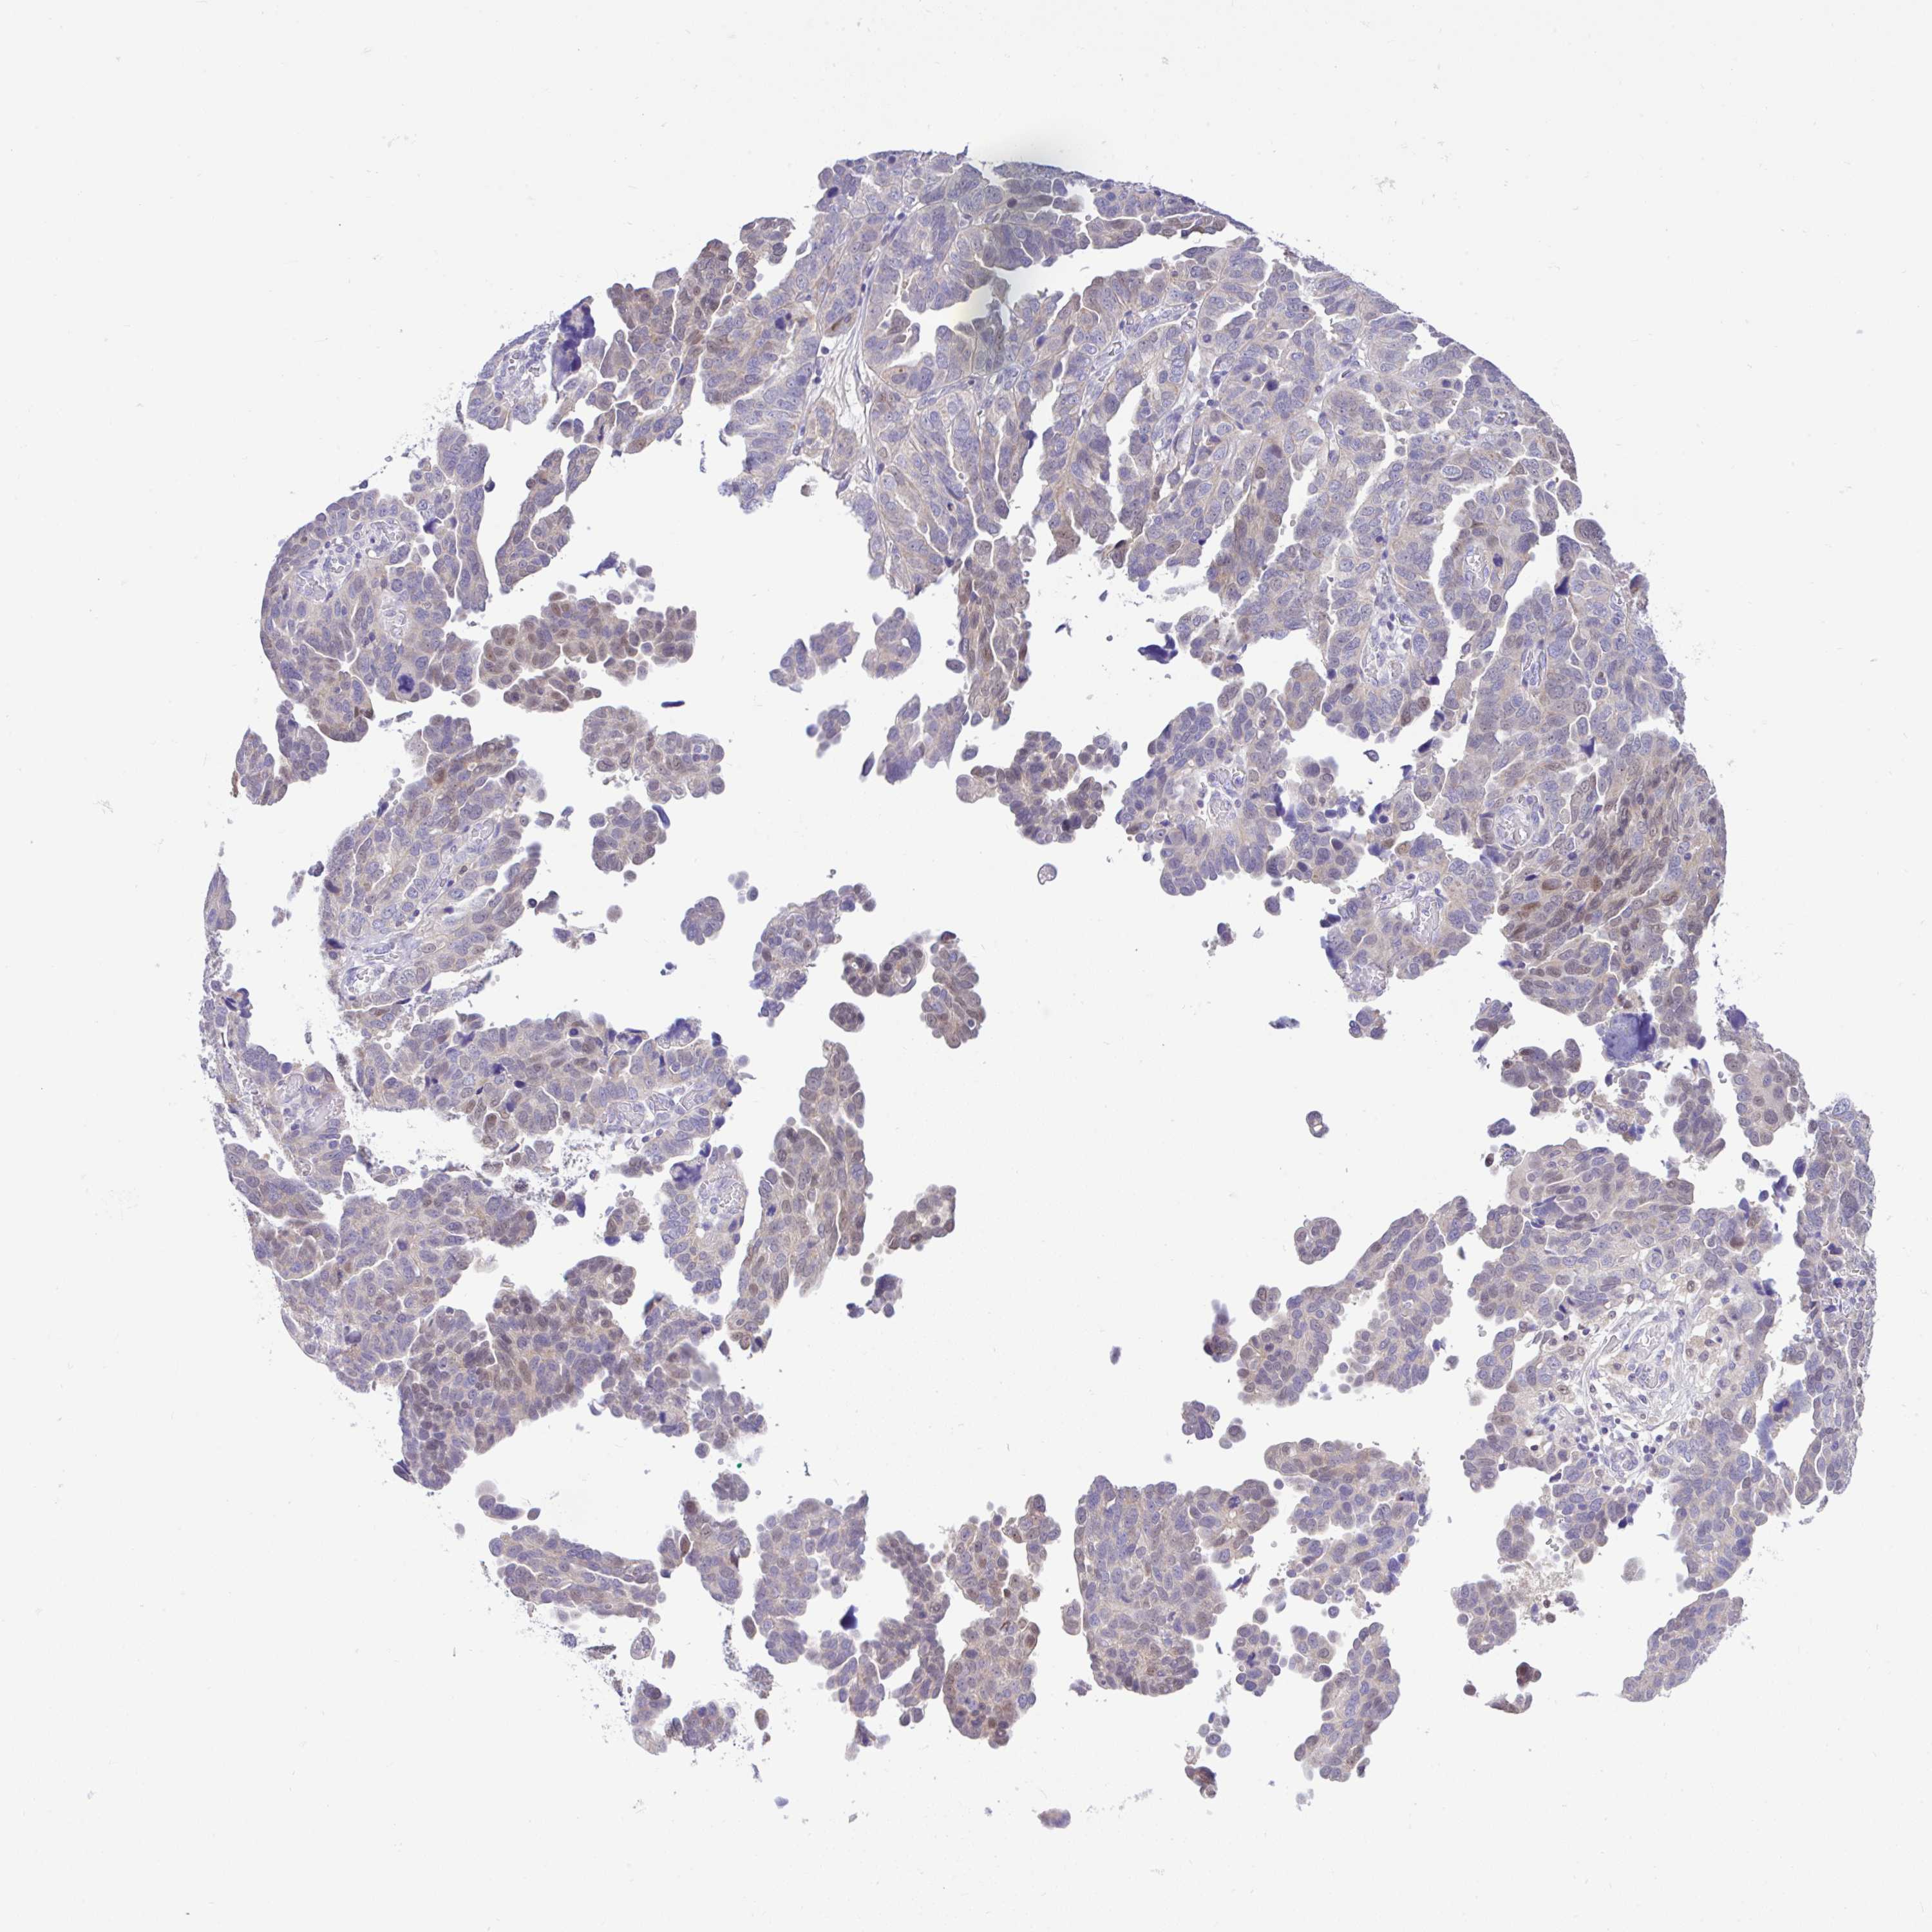

OVARIAN CANCER - Protein expressioni

A mouse-over function shows sample information and annotation data. Click on an image to view it in a full screen mode. Samples can be filtered based on level of antibody staining by selecting one or several of the following categories: high, medium, low and not detected. The assay and annotation is described here.

Note that samples used for immunohistochemistry by the Human Protein Atlas do not correspond to samples in the TCGA dataset.

Antibody stainingi

Antibody staining in the annotated cell types in the current human tissue is reported as not detected, low, medium, or high, based on conventional immunohistochemistry profiling in selected tissues. This score is based on the combination of the staining intensity and fraction of stained cells.

Each image is clickable and will lead to virtual microscopy that enables deeper exploration of all samples and also displays staining intensity scores, fraction scores and subcellular localization as well as patient and tissue information for each sample.

Antibody HPA053412

Staining

High

Medium

Low

Not detected

Intensity

Strong

Moderate

Weak

Negative

Quantity

>75%

75%-25%

<25%

None

Location

Nuclear

Cytoplasmic/membranous

Cytoplasmic/membranous,nuclear

Cystadenocarcinoma, serous, NOS

Cystadenocarcinoma, mucinous, NOS

Carcinoma, endometroid